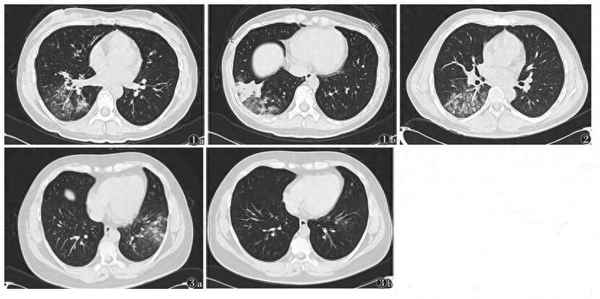

(此处已添加医疗卡片,请到今日头条客户端查看)下面是一个支原体肺炎的CT胶片:

支原体肺炎的CT表现